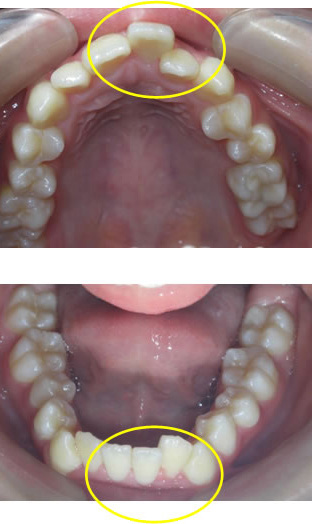

歯列弓の臼歯間幅径が狭いもの。

これには、臼歯が舌側に転位しているものと、顎骨自体が狭いものがある。

上顎では口蓋が深いものが多い。

(歯科矯正学 第4版 医師薬出版)

◎歯列の不正を伴う

◎上下顎骨の劣成長を伴う

◎口蓋幅の成長が少ない

◎歯列幅が狭い

◎低位舌を伴う

◎下顎が後方位

前歯の凸凹だけが問題なのでしょうか?

本来、この方が本来成長するはずであったところは上記のような上下顎のイメージになります!

顎が成長して(咀嚼や周囲の筋肉の調和などにより)歯が並ぶのに十分なスペースができさえすれば、乱れて生えてきた歯は自然に本来その歯が並ぶべき位置まで動いていってくれるという発想です。